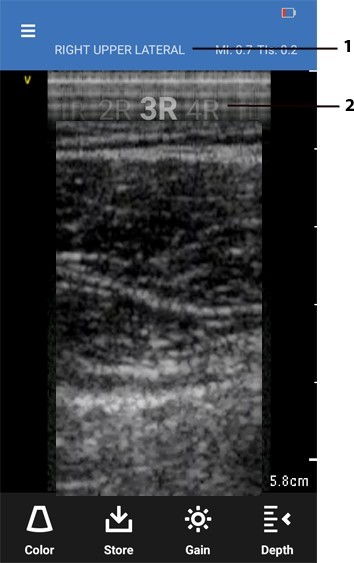

Lung protocol scan screen

- Displays current segment name

- Number and site indicator of current segment